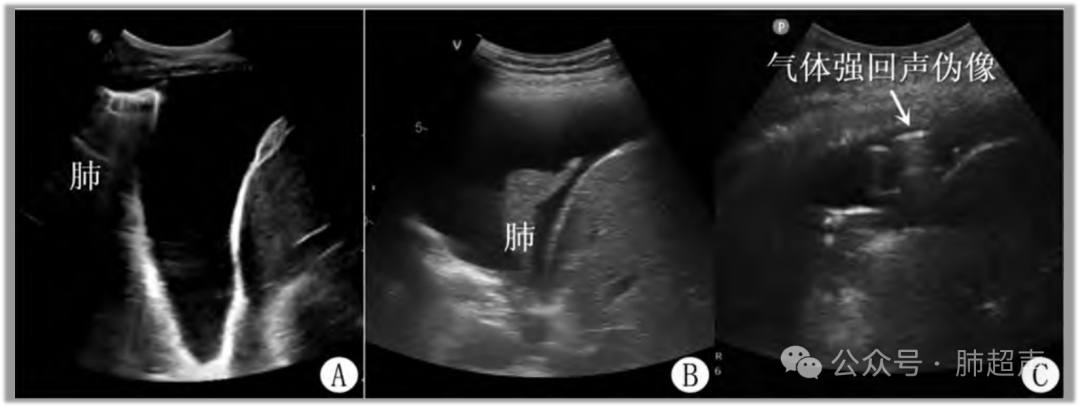

(4) 不同病原体肺炎超声表现有所不同,多发B线常见于病毒性肺炎、支原体肺炎等;大叶性肺实变常见于细菌性肺炎(图2)

图2  肺炎常见超声表现

注:A. 局部肺泡炎性渗出; B. 局灶性肺炎(B线)与周围正常肺充气(A线)并存; C. 肺炎渗出不均匀,局部小范围胸膜下肺泡塌陷呈实变; D. 大范围肺叶炎性渗出呈实变。